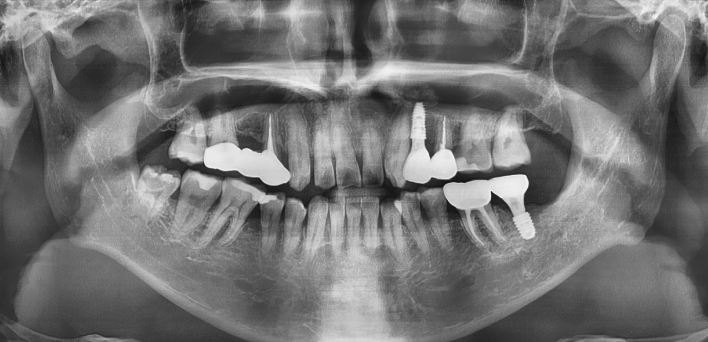

임플란트 : 손 ** 님 (50대)

치아가 있다는게, 아직도 정말 꿈만 같아요.

Before Before

2020.02.30

After After

※ 더서울치과의원은 의료법을 준수하며 위 케이스는 실제 환자의 동의를 얻은 사례로 치료 전, 후가 동일한 환경에서 촬영되었습니다.

환자 케이스에 따라 부작용이 발생할 수 있습니다. 이 부분은 의료진의 충분한 상담과 체크를 통해 예방하고 줄일 수 있습니다.

[임플란트 부작용] 수술 후 관리가 소홀할 경우 출혈, 주위염 등의 부작용이 발생할 수 있어 구강 위생을 철저히 유지하고, 정기적인 검진을 통해 상태를 점검하는 것이 중요합니다.

환자 특징

환자 특징01무치악 상태

환자 특징02수년간 무치악으로 지내심

임플란트가 불가능할것이라

생각하고 내원

위, 아래 6개씩 식립

디지털 풀아치 임플란트

임플란트 케이스

임플란트 Before & After